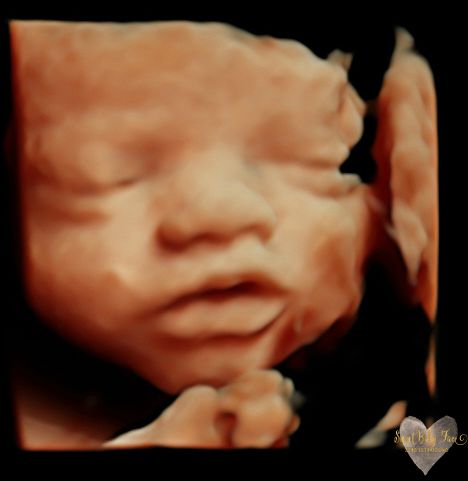

3D/4D/5D Ultrasound Gallery

Take a peek at our Photo Gallery. All of our 2D, 3D, 4D, HD elective ultrasound images are truly ours. They come directly off our machine from our highly trained staff. We can start getting great 3D/4D images as early as 10 weeks!